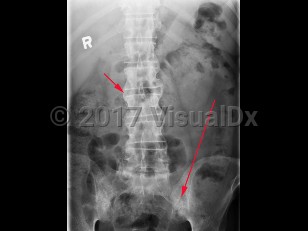

Ankylosing spondylitis is an autoimmune inflammatory disorder characterized by inflammation of the axial skeleton and peripheral joints. It typically begins in the second or third decade of life with a male-to-female prevalence of 2-3:1. There is a high concordance of ankylosing spondylitis in patients with haplotype human leukocyte antigen B27 (HLA-B27).

Patients most typically present with dull pain in the lower lumbar or gluteal region accompanied by early morning stiffness that improves with activity but not with rest. As the disease progresses, pain becomes persistent and bilateral and may worsen at night. Cervical ("chalk-stick") fractures may occur, especially after trauma. In addition to back pain, enthesitis (tenderness at the tendon or ligamentous insertion site to bone) may be common at the costosternal junction, spinous processes, iliac crests, greater trochanters, ischial tuberosities, tibial tuberosities, and heels. Approximately 30% of patients experience arthritis of peripheral joints other than the hips and shoulders. The most common extraarticular manifestation is acute anterior uveitis in up to 40% of patients. A large percentage of others may have inflammation of the terminal ileum or colon, although the majority of cases are asymptomatic. Only a minority of these patients progress to develop inflammatory bowel disease.

Physical examination findings reveal limited spinal mobility with limitation of anterior and lateral flexion / extension of the lumbar spine. Patients may also have limited chest wall expansion and tenderness at the tendinous insertion sites.